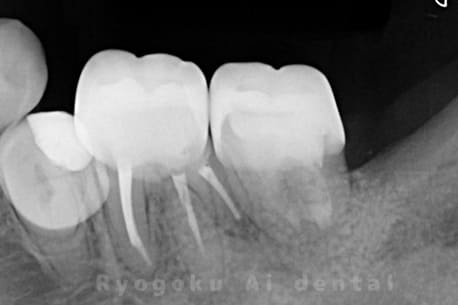

噛むと痛みが出る、とのことで来院した患者様です。他院での根管治療を終えてましたが、根尖病変を認めるため、マイクロエンドを行いました。

<リスク・副作用>

術後は痛み、腫れ、痺れなどの副作用が生じる場合があります。症状が再発する可能性があります。